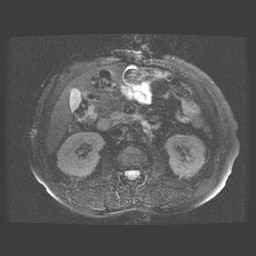

Abdomen

Angio abdominaal